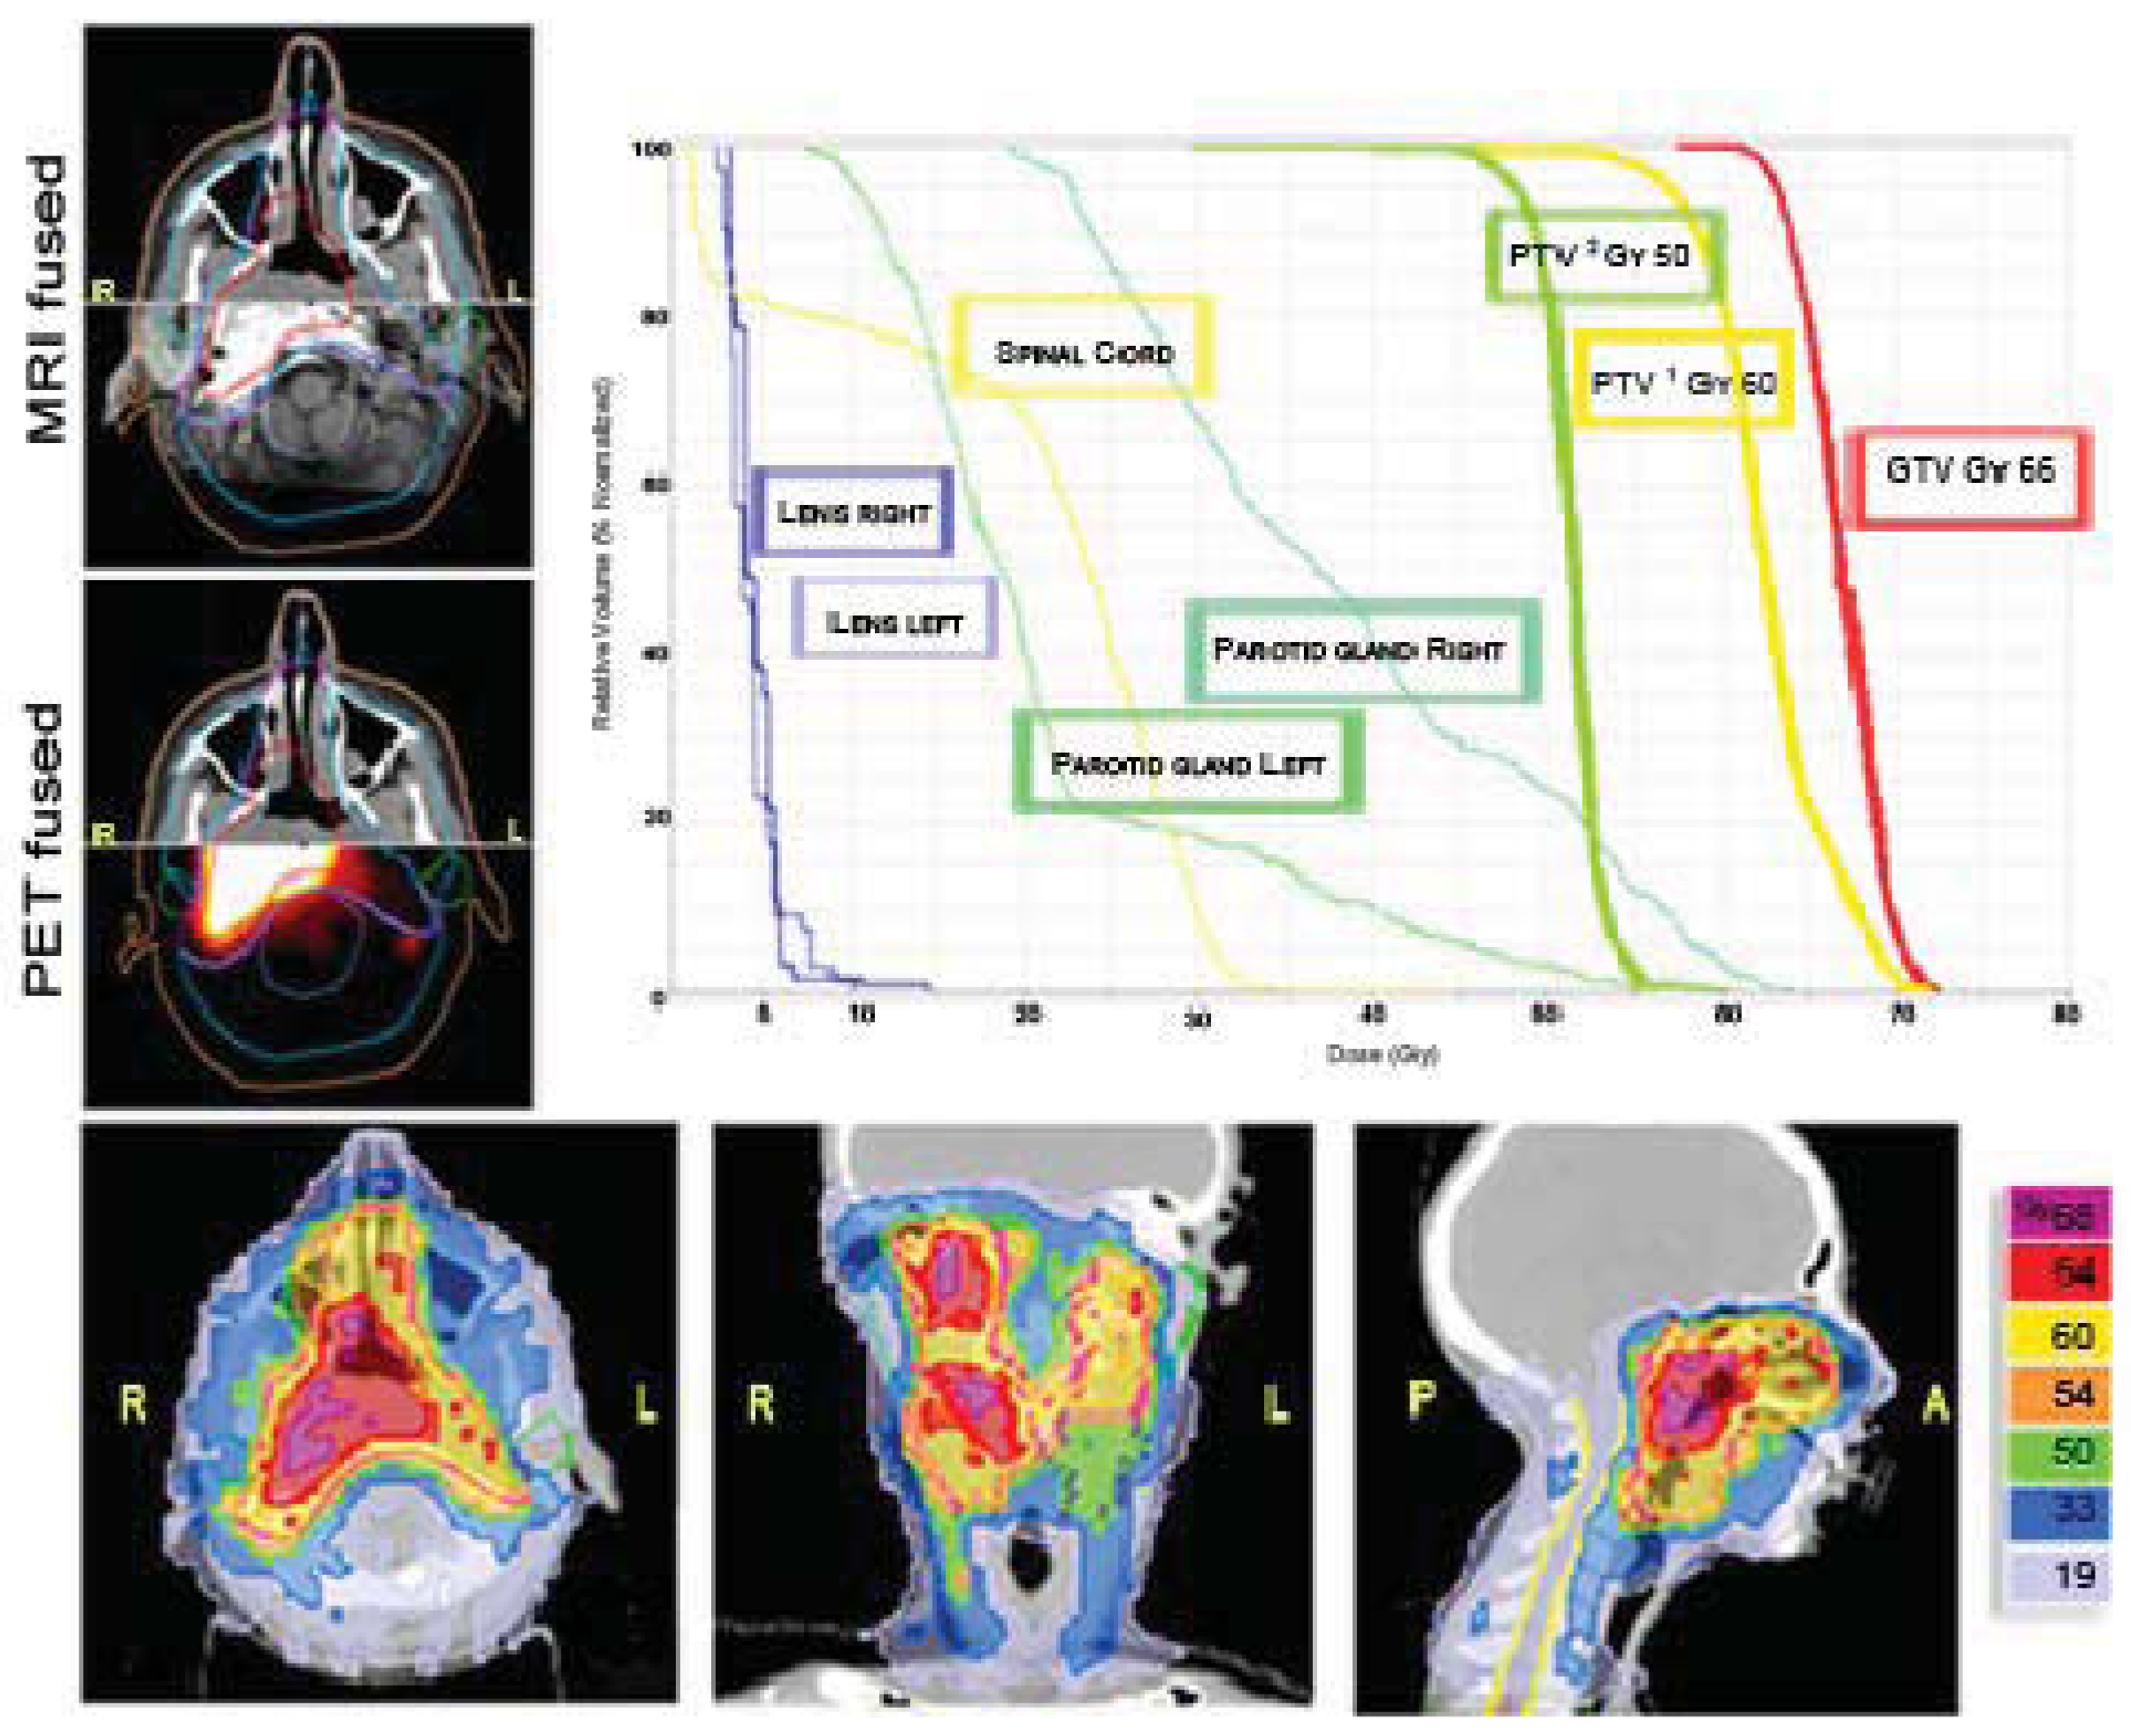

In our patients with head and neck tumors the use of HT, as an alternative to 3D-CRT, was chosen to avoid multiple fields, different energies, and junctions and to spare unavoidably higher dose to the optic nerves, chiasm, eyes and lens, as shown in our adolescent patient affected by esthesioneuroblastoma of the nasal cavity (Figure 5). HT gives us the opportunity to “paint” the high-dose region around the target volume and thus spare at least part of the mucosa from the high-dose region.

Cases like this demonstrate that HT-delivered IMRT may provide superior dose homogeneity and dose conformality when compared to earlier technologies, such as 3D-CRT or conventional RT, leading to efficient sparing of the spinal cord, the parotids, the teeth and the mandible.

An important point in favor of HT (and other IMRT methods) is the possibility to efficiently and easily deliver different doses at different volumes (Figure 6). The choice between IMRT delivered with Linac or with HT is random for head and neck tumors in our Department. Based on our adult experience, there is no difference between the two IMRT modalities in terms of loco-regional control and development of severe, acute, and late toxicities [19]. For both techniques the patient setup is done with CT images (MV-CT or cone-beam-CT).